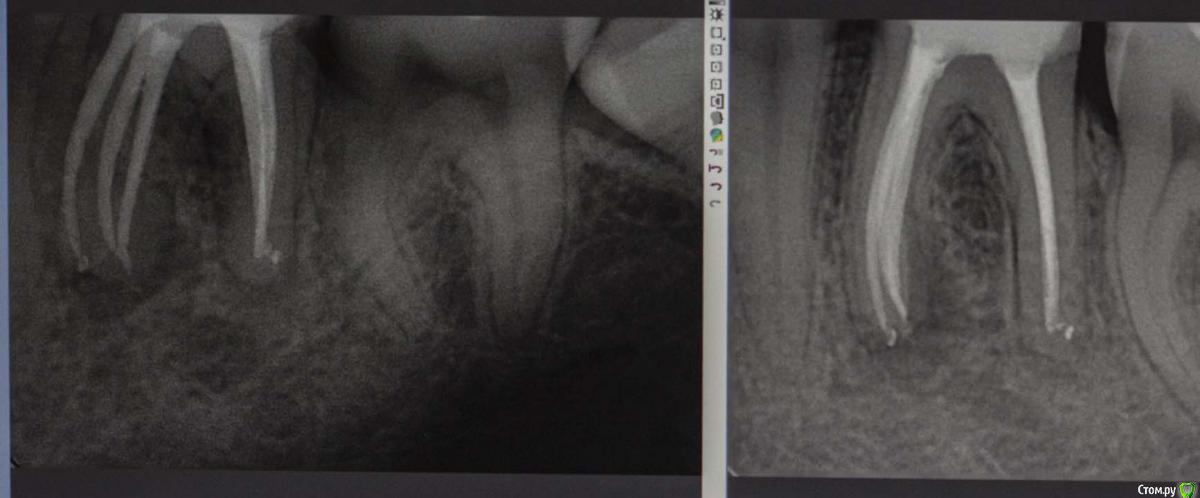

M@estro Опубликовано 19 марта, 2015 Автор Поделиться Опубликовано 19 марта, 2015 (изменено) Ну вот как - то так. Жалобы на эстетику. Зуб асимптоматичен, но я перебрал, уж сильно неплотно там было. В анамнезе резекция верхушки корня лет 7 назад. http://s016.radikal.ru/i334/1503/78/5a6341839e0c.jpg http://s013.radikal.ru/i323/1503/04/31d3729756de.jpg http://s018.radikal.ru/i524/1503/a9/79248c45e74b.jpg Изменено 19 марта, 2015 пользователем M@estro 13 Ссылка на комментарий